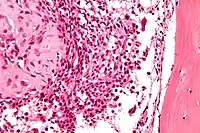

Micrograph of a chondroblastoma. H&E stain

Chondroid differentiation is a common feature of chondroblastoma.[10][12][13] A typical histological appearance consists of a combination of oval mononuclear and multi-nucleated osteoclast-type giant cells.[10][7][12] However this is not a prerequisite for diagnosis, as cells with epithelioid characteristics have been observed in lesions of the skull and facial bones.[12] A "chicken-wire" appearance is characteristic of chondroblastoma cells and is the result of dystrophic calcification that may surround individual cells.[10][14] Although, calcification may not be present and is not a prerequisite for diagnosis.[10][7][12] Mitotic figures can be observed in chondroblastoma tissue but are not considered atypical in nature, and therefore, should not be viewed as a sign of a more serious pathology.[10][12] There is no correlation between mitotic activity and location of the lesion.[12] Furthermore, the presence of atypical cells is rare and is not associated with malignant chondroblastoma.[10][13] There are no discernible histological differences observed when comparing the aggressive form of chondroblastoma that can cause recurrence or metastases with its less aggressive, benign, counterpart.